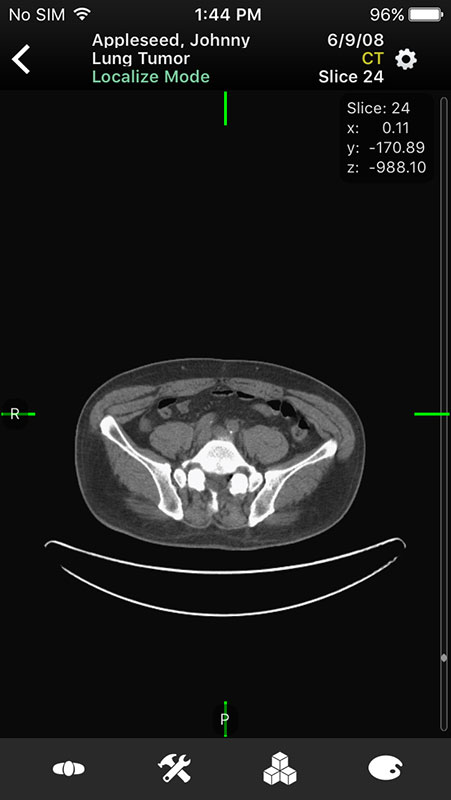

These sample images feature same imaginary patients and cases from the Mobile MIM app and contain X-ray, PETCT, MR, and ultrasound scans, alongside the name of the procedure.

Just like in Mobile MIM app, images open in multi-planar view allowing users to choose series depending on the type of imaging technique, add annotation, or measure the image.

For example, flicking screen right or left enables users to switch between series, planes, and images, while swiping up and down switches between planes, or images in the series (with 2D images).